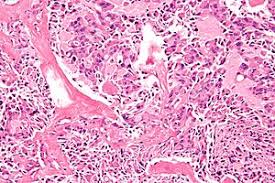

Congo red histological staining is the gold standard technique for the detection of amyloidosis. Staining with congo red (cr) is a qualitative method used for the identification of amyloids in vitro and in tissue sections. Cytokeratin (ck) staining can be used to identify the amyloid as epidermal in origin. Congo red histological staining technique is the gold standard technique for the diagnosis of amyloidosis. Place slides in solution a: At what um should these sections be cut at? • congo red congo red histology stain is used to stain amyloid. The diagnosis of amyloid requires an experienced laboratory, as false negative and false positive diagnoses on the basis of histology are not infrequent.

The history of congo red december 9, 2019 congo red is the essential histologic stain for demonstrating the presence of amyloidosis in fixed tissues. Congo red method the main special stain used for amyloid detection is congo red. • cresyl violet this histology stain is a nissl stain. Amyloid in vessel wall apple green with polarized light. In contrast to amyloidosis, colloid milium is negative for laminin and type iv collagen. Histology congo red amyloid stain badge reel with a colored glass bead! When stained with the congo red stain the amyloid, with the aide of polarizing lenses, will birefringe an apple green color. It stains cell bodies a blue/violet. It is a dye belongs to a group of azo dyes derived from benzidine and it does not require the application of mordant. Congo red, the same image is seen before but with a light microscope Send block containing tissue biopsy (fixed in 10% formalin and paraffin embedded) (congo red x 100) discussion lichen amyloidosis is the most common variant of primary cutaneous amyloidosis (pca) and is associated with the extracellular deposition of amyloid in the skin without associated internal organ involvement. Special studies for colloid milium.

At what um should these sections be cut at? Congo red histological staining is the gold standard technique for the detection of amyloidosis. Cytokeratin (ck) staining can be used to identify the amyloid as epidermal in origin. Amyloid p has a sensitivity of 100% and specificity of 95%. Perfect for work, school, or convention badges. Colored glass bead may vary based on what i have on hand, but ill try to match the frame color or overall color scheme! Amyloid is homogeneous and eosinophilic, the deposits are extracellular and may become sufficiently large enough to cause damage to surrounding tissues. Name another stain that stains the same 4. (congo red x 100) discussion lichen amyloidosis is the most common variant of primary cutaneous amyloidosis (pca) and is associated with the extracellular deposition of amyloid in the skin without associated internal organ involvement. Place slides in a plastic coplin jar containing solution a: The diagnosis of amyloid requires an experienced laboratory, as false negative and false positive diagnoses on the basis of histology are not infrequent. • cresyl violet this histology stain is a nissl stain. Congo red dye binds to fibrils and form a regular pattern of dye molecules during the process.

Since the 1920s, congo red dye was shown to specifically stain amyloid deposits in tissue and has been considered the pathologic gold standard for amyloid disease. Congo red was positive in 25/45 (56%) and was negative in 20/45 (44%). Cytokeratin (ck) staining can be used to identify the amyloid as epidermal in origin. The reason for this is that the congo red dye used in the stain is highly selective for amyloid deposits, which can lead to amyloidosis and also alzheimers. Congo red is still the standard stain used in most histopathology laboratories to identify amyloid material in tissues.

Congo red stain (left) and serum amyloid a immunohistochemistry (right), 100x. Congo red stain is the gold standard for the demonstration of amyloid in tissue sections it is used to evaluate the presence and extent of amyloidosis in different organs common diseases for congo red stain include primary amyloidosis, al amyloid seen in plasma cell dyscrasias, aa amyloid associated with inflammatory conditions It is a dye belongs to a group of azo dyes derived from benzidine and it does not require the application of mordant. Congo red histological staining is the gold standard technique for the detection of amyloidosis. However, in the histology world cr is used to stain amyloid. (congo red x 100) discussion lichen amyloidosis is the most common variant of primary cutaneous amyloidosis (pca) and is associated with the extracellular deposition of amyloid in the skin without associated internal organ involvement. At what um should these sections be cut at? Cytokeratin is positive in lichen amyloidosis and. Histology special stains submission details: Name another stain that stains the same 4. • cresyl violet this histology stain is a nissl stain. Congo red, the same image is seen before but with a light microscope Congo red is a synthetic dye, used for the differential staining of elastic fibers.